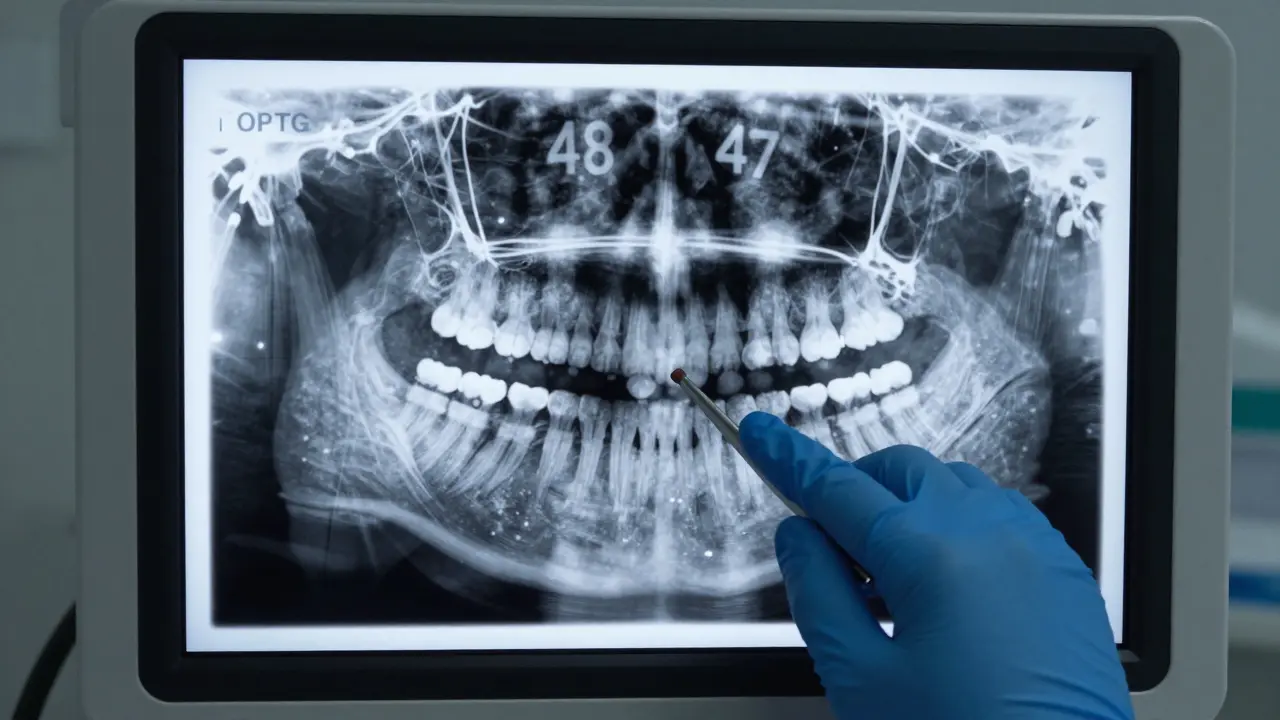

Rentgenový snímek čelisti ukazující impaktovaný zub 48.

Zkušený stomatolog rozhodne o odstranění zubu 48 na základě rentgenového snímku (často pomocí panoramatického snímku, tzv. OPTG). Pokud lékař vidí, že zub roste v šikmém úhlu, je riziko poškození sousedních tkání příliš velké a vytržení je jedinou racionální cestou.